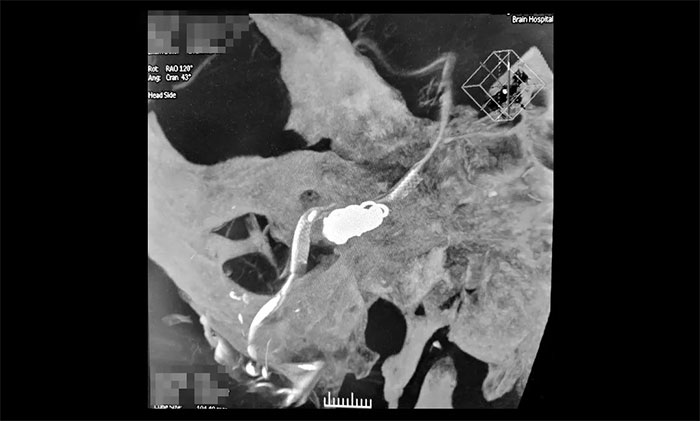

術(shù)中,席剛明教授在王貴平博士協(xié)助下,克服血管迂曲等困難,在微導管到位后緩慢釋放Pipeline血流導向裝置到達術(shù)前預定位置,右椎動脈V4近段。隨后,通過Echelon-10微導管行動脈瘤栓塞,向右側(cè)椎動脈瘤內(nèi)填入大小不同的彈簧圈共計3枚,造影提示右側(cè)椎動脈夾層動脈瘤顯影減慢減少、瘤內(nèi)造影劑滯留,右椎動脈、基底動脈、右側(cè)小腦后下動脈、右側(cè)小腦前下動脈顯影可。行3D造影見右椎動脈、左椎動脈V4段、基底動脈、雙側(cè)大腦后動脈、雙側(cè)小腦上動脈、雙側(cè)小腦前下動脈、雙側(cè)小腦后下動脈顯影可;行支架CT見支架成形滿意。術(shù)后CT檢查,顱內(nèi)未見出血,手術(shù)順利完成,患者獲得了理想的血管重建。術(shù)后,患者順利蘇醒,無新發(fā)神經(jīng)功能缺損。目前,患者已康復出院,計劃術(shù)后3個月隨訪。

▲ 血流導向裝置置入、彈簧圈栓塞后